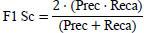

To evaluate the quality of the suggested model segmentation, we employed pixel-level metrics including accuracy, Dice coefficient, IoU, precision, recall, and F1 score. Table 3 represents the definitions of the metrics.

| S.No. | Metrics | Definition |

|---|---|---|

| 1. | Dice Score |

|

| 2. | Accuracy |

[32] [32]ee: True Positives, ff: True Negatives, nn: False Positives, mm: False Negatives |

| 3. | Precision |

|

| 4. | Recall |

|

| 5. | F1-Score |

[33] [33]

|

| 6. | IOU |

|